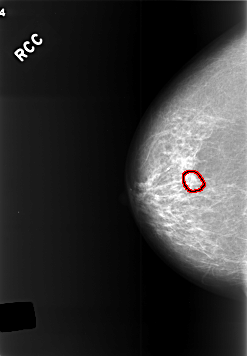

C_0412_1.RIGHT_CC

RIGHT_CC LINES 5696 PIXELS_PER_LINE 3952 BITS_PER_PIXEL 12 RESOLUTION 50 OVERLAY

FILE: C_0412_1.RIGHT_CC.OVERLAY

TOTAL_ABNORMALITIES 1

ABNORMALITY 1

LESION_TYPE CALCIFICATION TYPE PLEOMORPHIC DISTRIBUTION CLUSTERED

ASSESSMENT 3

SUBTLETY 3

PATHOLOGY BENIGN

TOTAL_OUTLINES 1

BOUNDARY